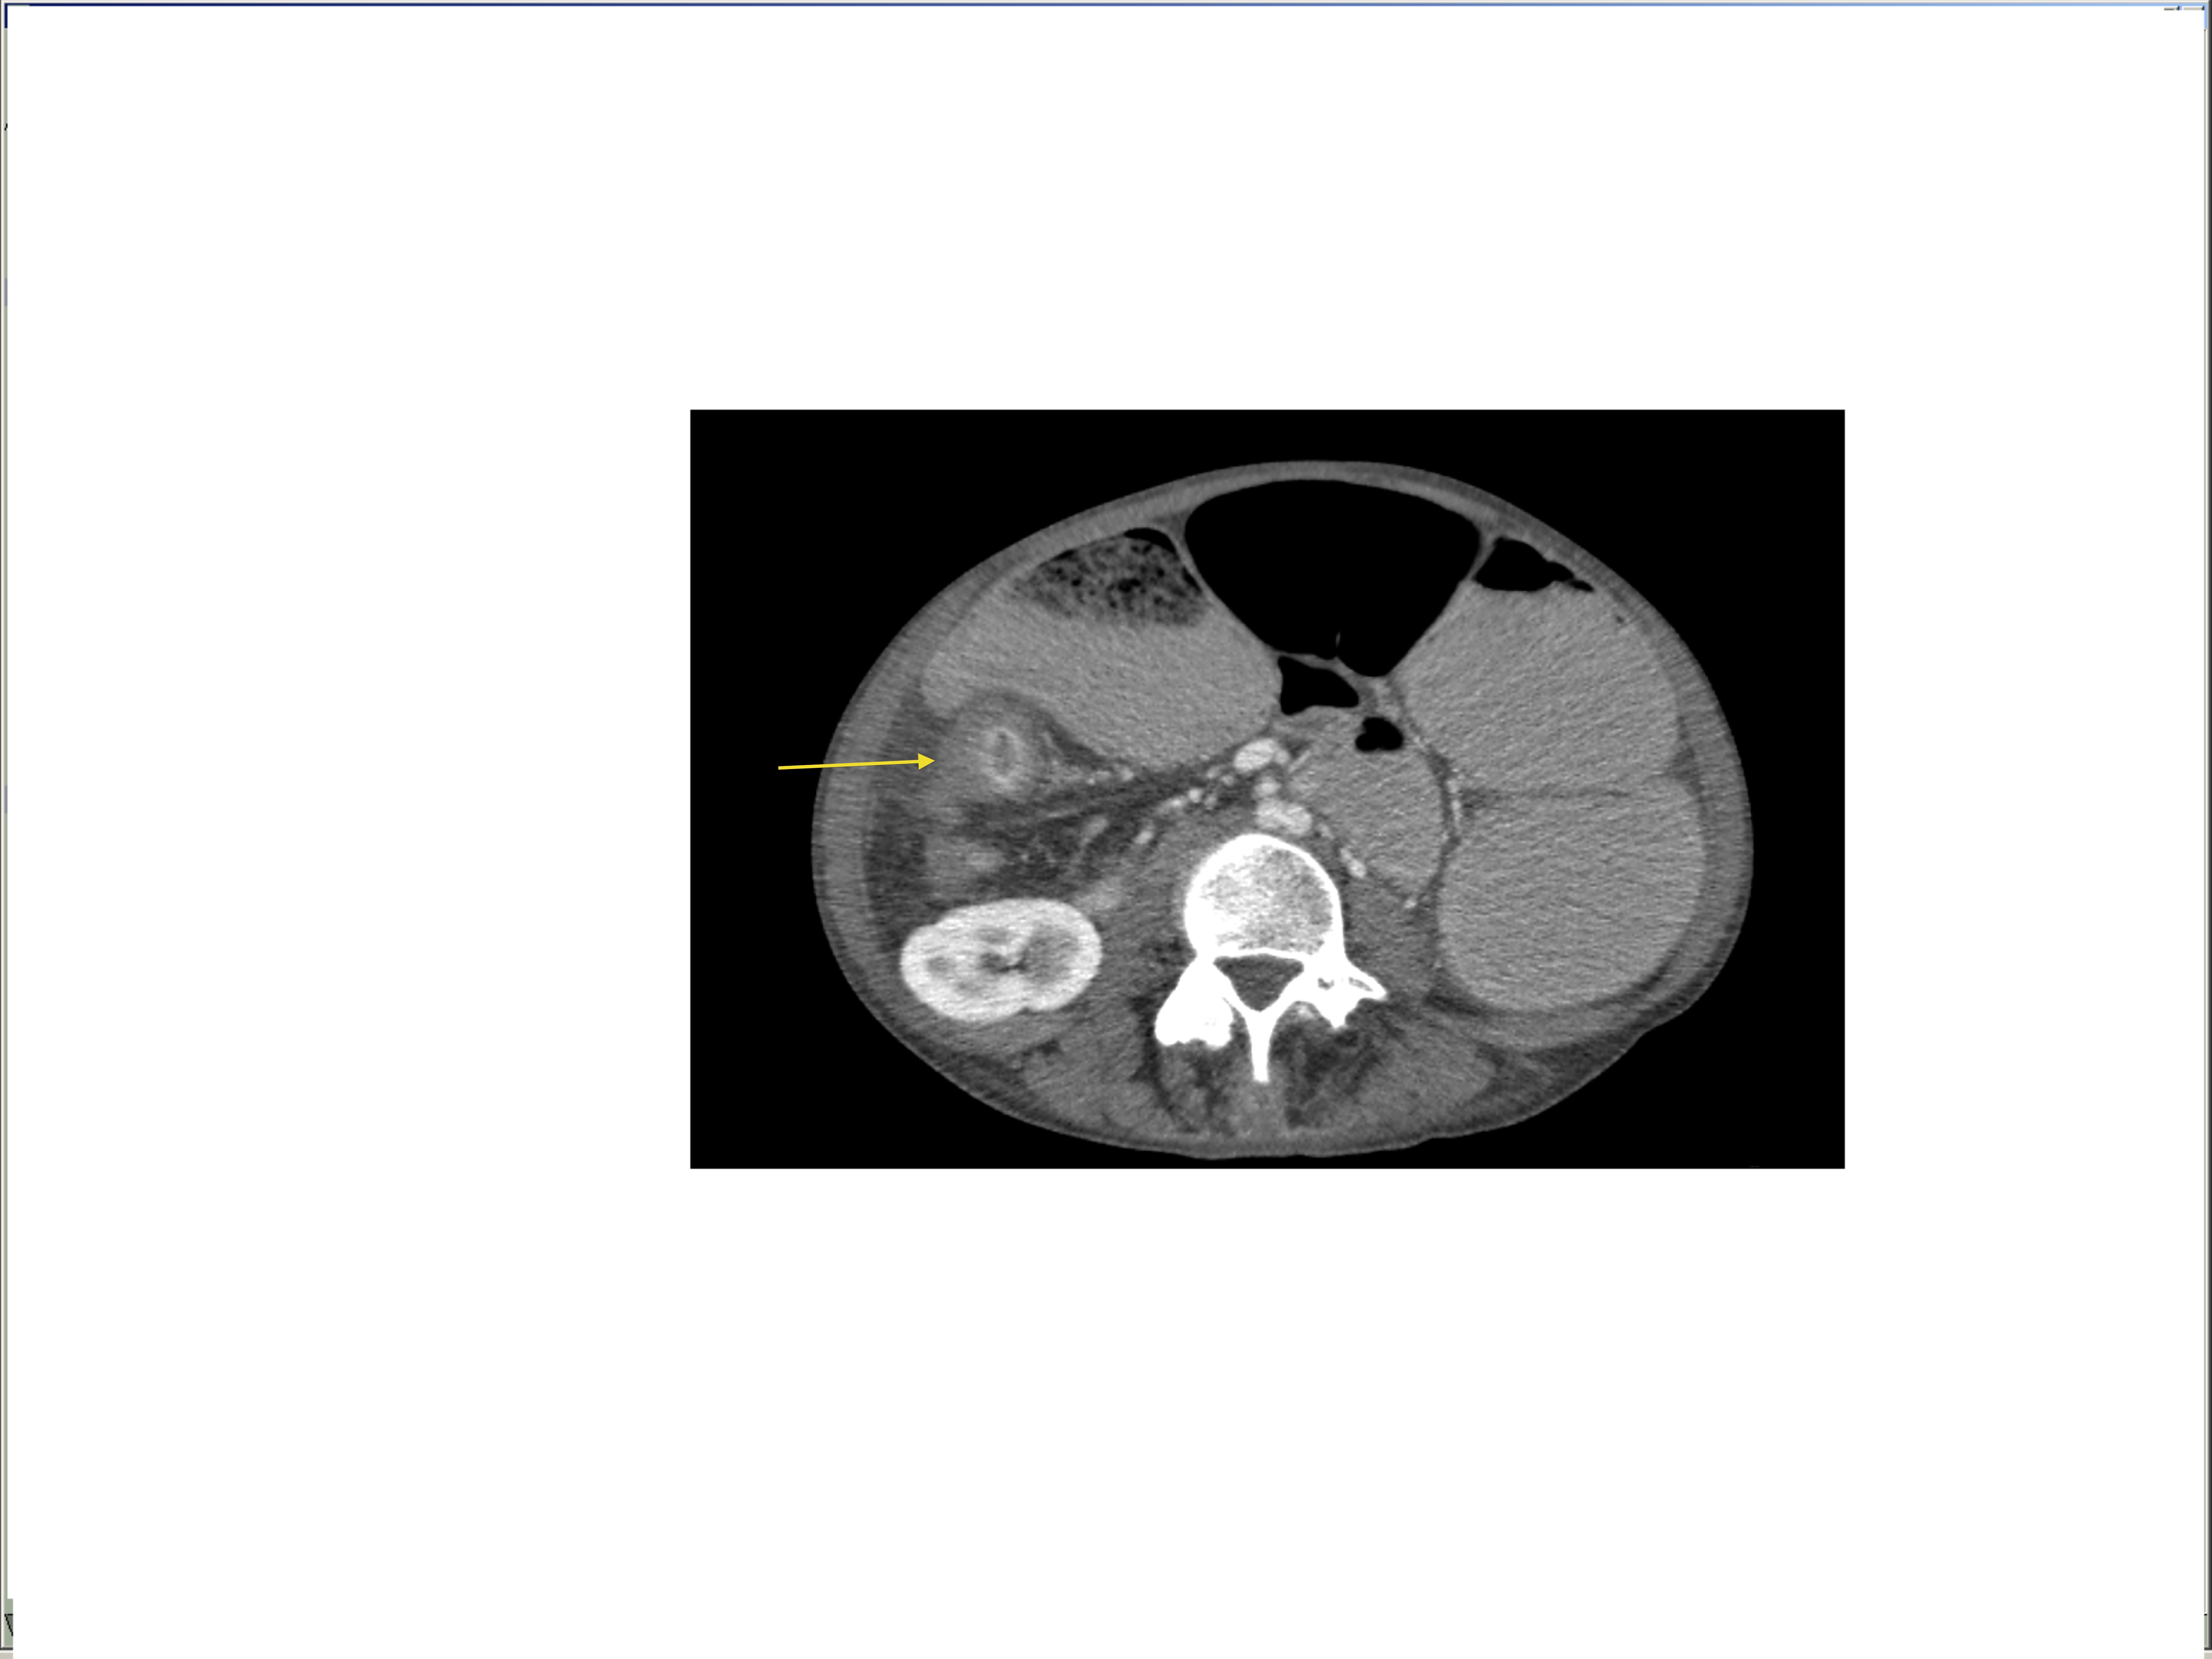

Small bowel obstruction is a common clinical presentation that presents a diagnostic conundrum. Over the last 2 decades, there has been a paradigm shift in the radiological investigation of small bowel obstruction (SBO) and in the indication for and timing of surgical intervention. Cross sectional imaging (predominantly computed tomography) has largely replaced the widespread use of radiographic small bowel follow-through studies as the imaging modality of choice for SBO. This article illustrates the current imaging modalities available for diagnosis of small bowel obstruction. (Full text available online at www.medpharm.tandfonline.com/ojfp) S Afr Fam Pract 2015; DOI: /10.1080/20786190.2014.977052